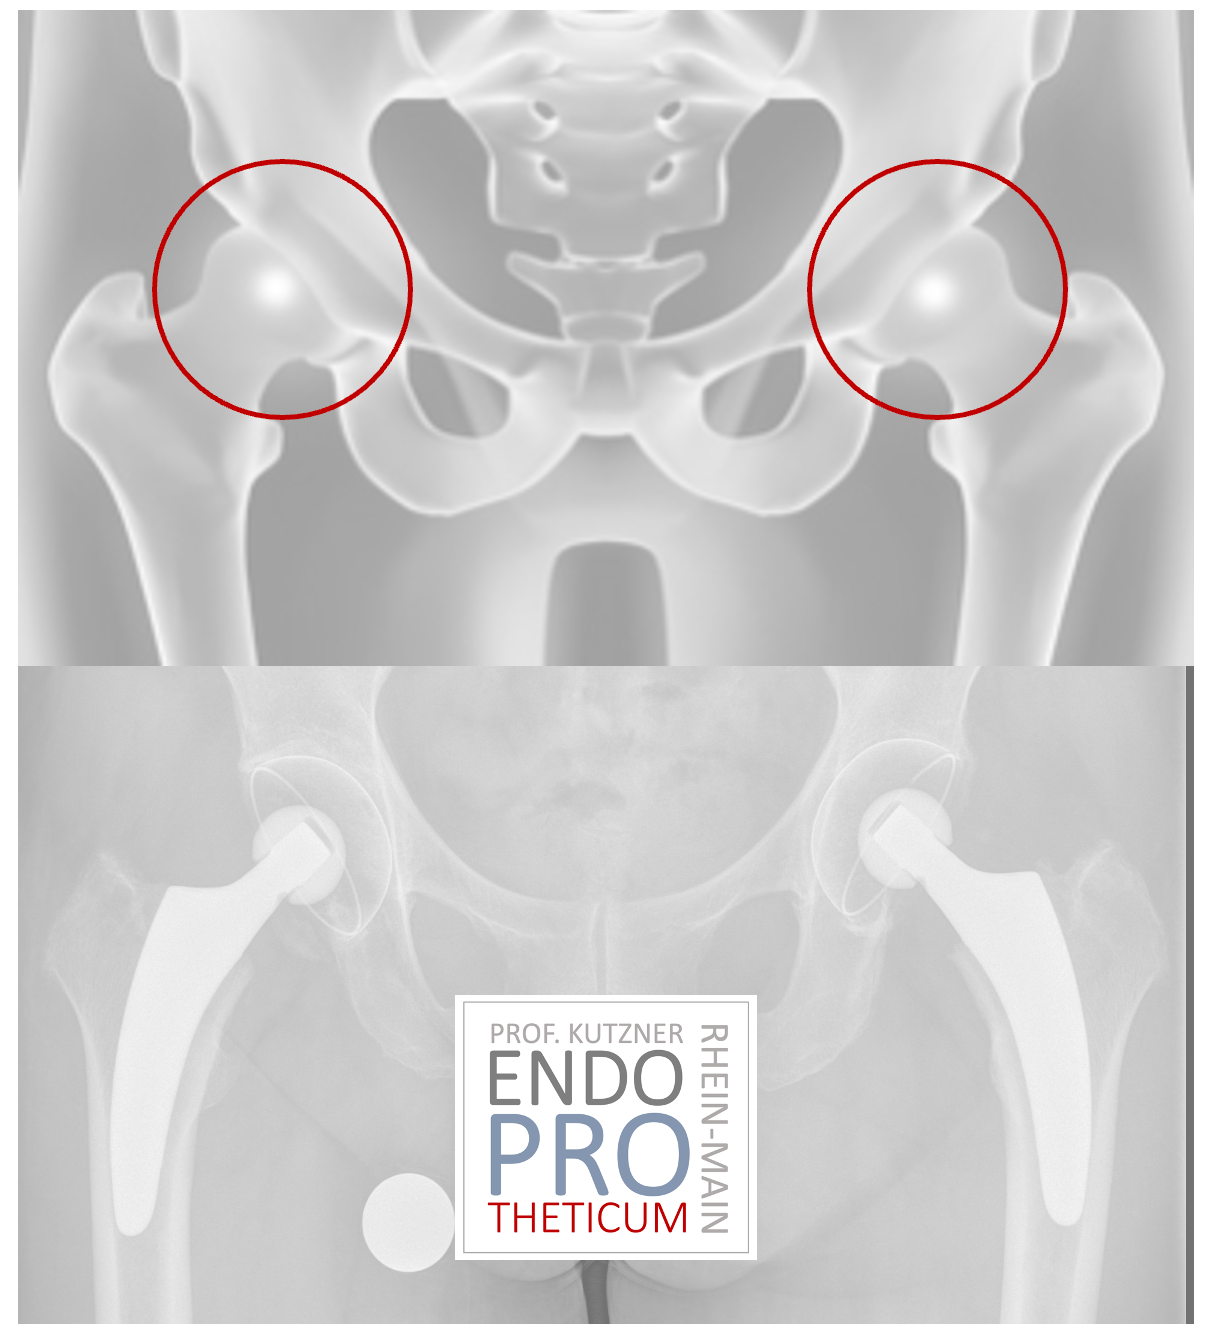

Les prothèses à tige courte sont devenues de plus en plus populaires ces dernières années. L'implantation d'une PROTHÈSE à tige courte vise à préserver l'os et à créer des conditions favorables à la révision sans changer les concepts de base de l'arthroplastie conventionnelle de la hanche.

Le concept de tiges courtes modernes guidées par le calcar dans l'arthroplastie de la hanche vise à la reconstruction précise de la géométrie anatomique individuelle de la hanche. Une technique d'implantation douce pour les os et les tissus mous est utilisée en association avec une mise en charge physiologique dans la partie du fémur proche de l'articulation afin de préserver l'os à long terme.